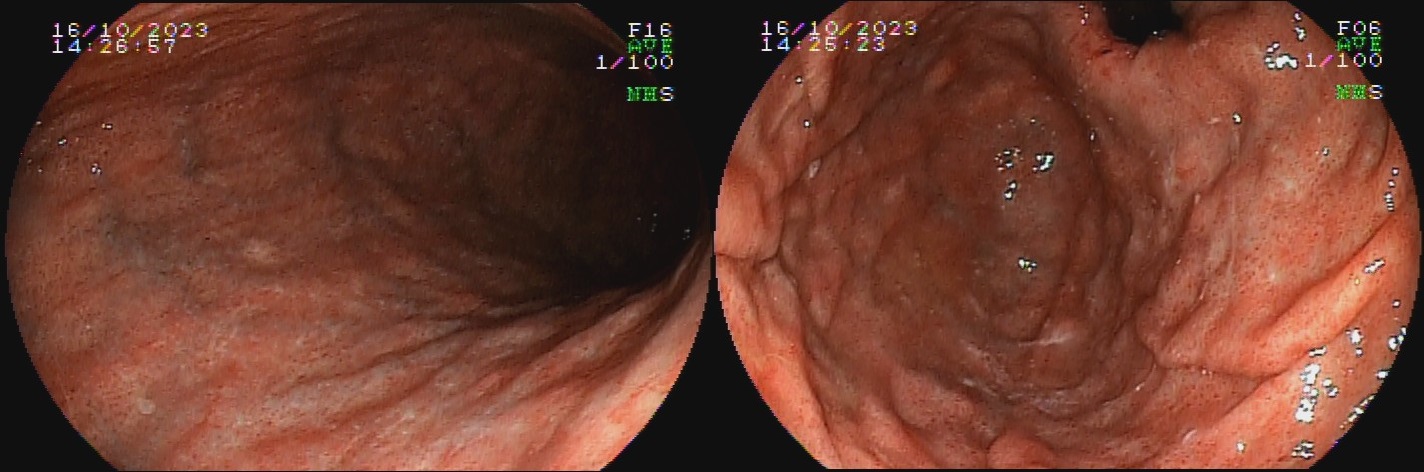

Já a gastrite atrófica autoimune ocorre por destruição glandular por autoanticorpos anticélulas parietais, e é mais comum em mulheres, porém dados relativos à idade e etnia mais frequente são controversos. A inflamação crônica resulta em redução do relevo e palidez da mucosa de fundo e corpo, assim como desaparecimento do pregueado mucoso observado à insuflação durante o exame endoscópico, com aspecto mais homogêneo que aquele encontrado na gastrite atrófica infecciosa. Podem ser formadas ilhas de mucosa normal residual, caracterizadas endoscopicamente como pseudopólipos. A mucosa do antro mantém-se preservada por não apresentar células parietais, delimitando uma área de transição clara entre a mucosa atrófica do corpo e mucosa normal do antro.